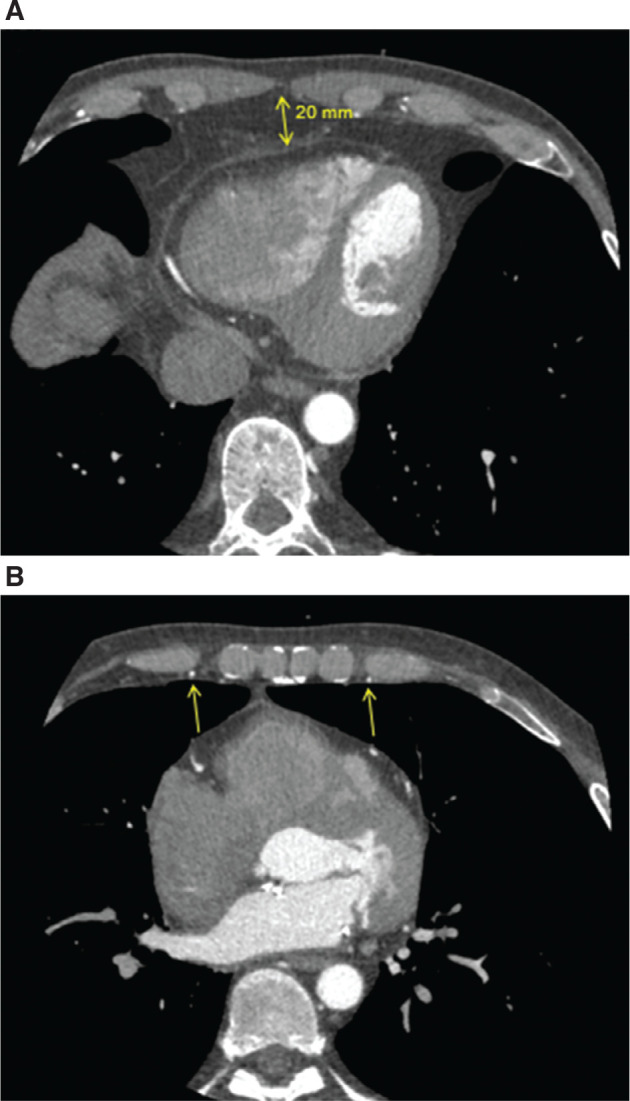

We present the case of a 52-year-old man suffering from malignant mitral valve prolapse syndrome. He underwent a right-sided thoracotomy for mitral valve repair but required implantable cardioverter-defibrillator (ICD) implantation 4 years later. He chose the option of a substernal ICD, which was implanted successfully without any complications and good electrical parameters.